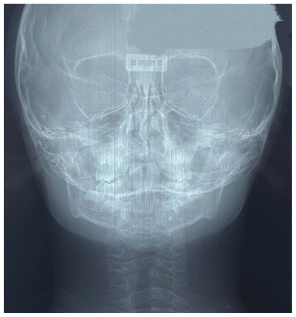

The patient was a young female presenting with a Class III dento-skeletal malocclusion, which was treated using the AMCOP® TC appliance. A comprehensive diagnostic protocol was carried out both before and after treatment, including orthopantomography (Figure 2–3), postero-anterior teleradiography (Figures 4, 5), latero-lateral cephalometric radiography (Figures 6, 7), cephalometric analysis (Tables 1, 2), as well as extraoral (Figures 8, 9) and intraoral photographs (Figures 10, 11). The extraoral examination revealed an edge-to-edge incisal relationship and the presence of a midline diastema. Pre-treatment cephalometric analysis (Deltadent® Lana, Bolzano, Italy) confirmed the diagnosis of a skeletal Class III malocclusion. The treatment plan involved the use of the AMCOP® TC appliance. The patient was instructed to wear the device for two hours in the afternoon and throughout the night for the first six months, followed by nighttime use only for an additional six months. Upon completion of the treatment, the patient achieved a Class I occlusion, with correction of both overjet and overbite. Additionally, the device facilitated tongue re-education and contributed to the postural realignment of the first cervical vertebra.